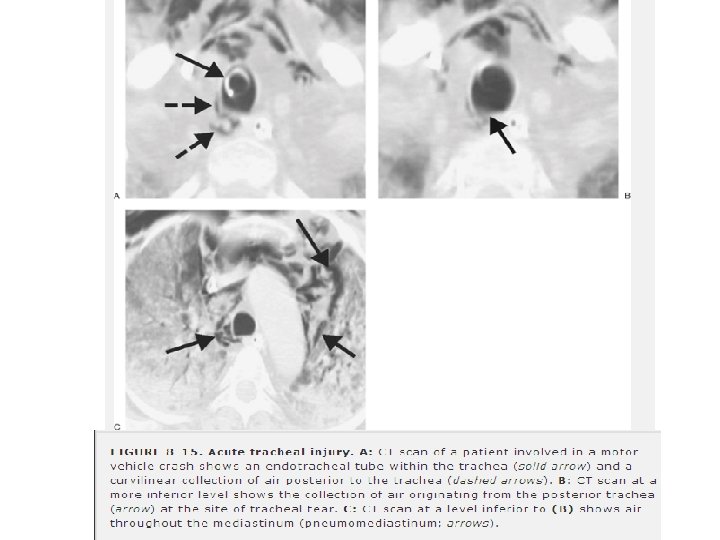

D. TRAKEABRONŞİAL AĞAÇ YARALANMALARI • Nadir ancak potansiyel olarak fataldir. (Mortalite yüksek) • Sıkça gözden kaçar. • Künt travmada, yaralanmaların büyük bölümü karinanın 1. 5 cm’lik mesafesi içinde meydana gelir. • Mortalite oranı yüksektir. • Trakeabronşial yaralanma şüphesi acil cerrahi konsültasyon gerektirir. • Hemoptizi, subkutan amfizem veya mediastinal şiftle birlikte TP varsa şüphelenilmelidir. • Tüp torakostomi sonrası fazla miktarda hava kaçağı devam eden pnömotorakslı hastalarda trakeabronşial yaralanmadan şüphelenilmelidir.

� Genellikle, hava kaçağını yenmek ve akciğeri genişletebilmek için, birden çok göğüs tüpü takmak gerekir. � Bronkoskopi tanıyı doğrular. � Karşı ana bronşun entübasyonu gerekir. � Zor entübasyon, �paratrakeal hematom, �eşlik eden orofarengial yaralanma �trakeobronşial yaralanmadan kaynaklanan anatomic bozulmalar nedeniyle � Çoğu hasta için acil cerrahi endikedir. � Stabil hastalarda akut inflamasyon ve ödem çözülünceye kadar operasyon ertelenebilir.